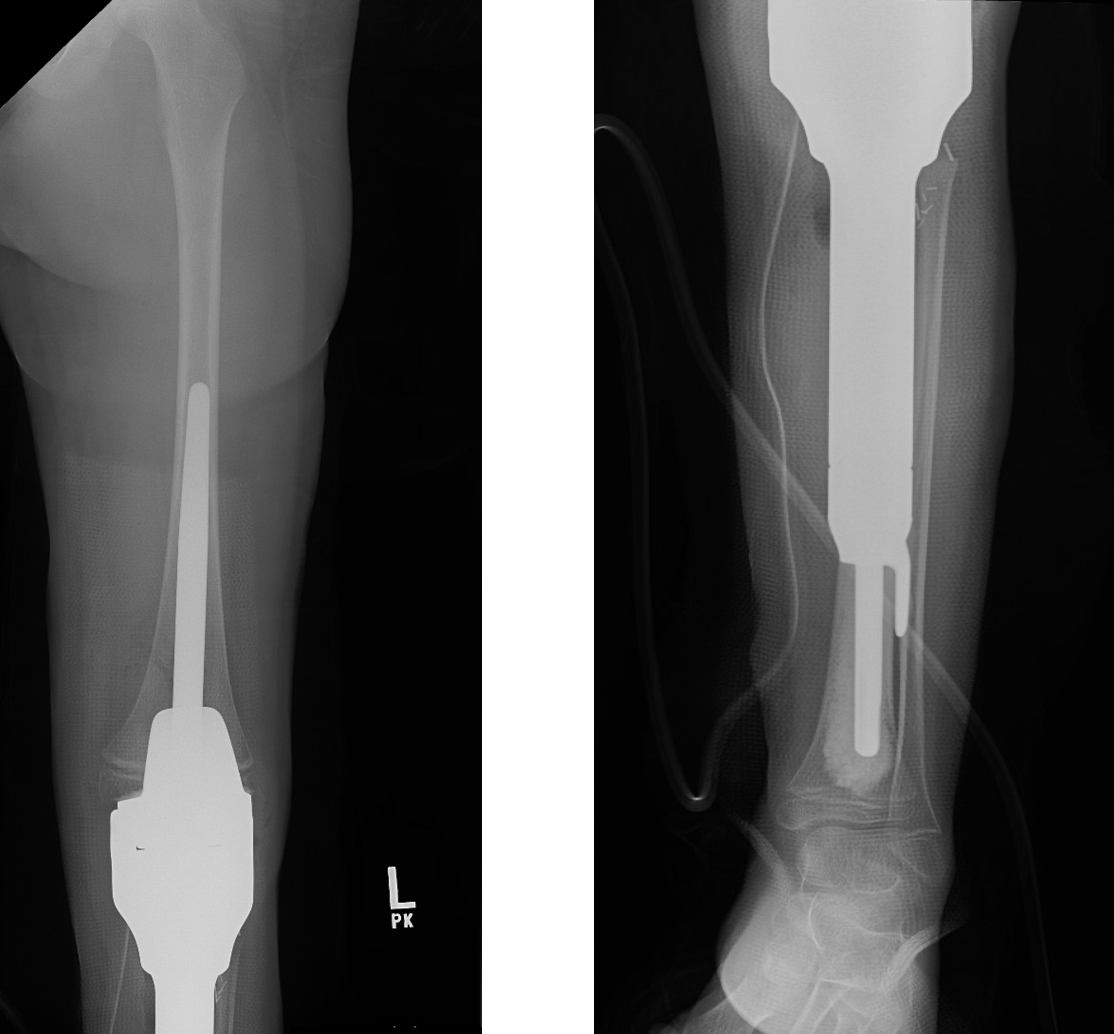

This is an x-ray image of the tibial prosthesis post-surgically.

The prosthesis is inserted to match the length of the diseased bone removed and the prosthesis joint is attached to the upper femur bone.